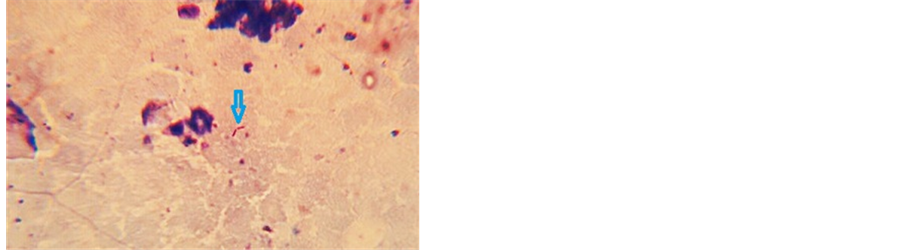

Physical examination revealed a large mass approximately 6 cm in diameter involving almost the entire right breast. The overlying nipple areola complex was scarred with evidence of ulceration (Figure 1). The mobility of mass within the breast and on the underlying muscle was restricted. Ipsilateral axilla did not reveal any lymphadenopathy clinically. Contralateral breast and axilla were normal. There was no evidence of cervical lymphadenopathy or spinal tenderness. Respiratory system did not reveal any abnormality. FNAC was done and confirmed the diagnosis of invasive ductal carcinoma. Special staining of the blood stained fluid from the ulcerated area revealed the presence of acid fast bacteria (Figure 2). Metastatic work up did not reveal any metastasis. Patient underwent two cycles of chemotherapy (CMF regime) preoperatively in order to downstage the locally advanced lesion. 25% regression in the size of the mass was observed after chemotherapy. Patient was then subjected to modified radical mastectomy with axillary clearance.

Figure 2. Acid fast bacteria marked by the blue arrow seen in the discharge from the ulcerated area (Zeihl Nelson staining, magnification ×100).

Tuberculosis of the breast is traditionally described as a great masquerader [1] -[4] . This is because it may present with a mass to begin with or a septic lesion in the form of an abscess. Either of them eventually ends up with the formation of a sinus. It can cause deformity of nipple areola complex as well as extensive scarring of the overlying breast. A scarred breast or a grossly deformed nipple areola complex as was seen in the case presented should raise the suspicion of tuberculosis. However these findings closely simulate malignancy making diagnosis extremely difficulty. Lump in the breast always merits prompt investigation by an FNAC. FNAC has high sensitivity and specificity in the diagnosis of breast cancer. However the diagnostic efficacy of FNAC in tuberculosis of breast is limited. Presence of epitheloid cells may be suggestive but in majority of cases these cells are usually not picked up [3] . Presence of caseating granulomas is diagnostic of TB but this necessitates elaborate histopathological evaluation [4] . Detection of acid fast bacilli in the lesions on the tissue culture or in discharge is diagnostic of tuberculosis [1] . In the case presented AFB were detected on examination of the blood stained discharge from the ulcerated area (Figure 2). However in practice many a times it is difficult to detect acid fast bacilli in the lesion. Review of articles on Google scholar and PubMed databases have revealed very few number of cases describing coexistence of tuberculosis and cancer in same breast. The coexistence of tuberculosis of the axillary lymph nodes along with breast cancer supersedes the incidence of coexistence of tuberculosis and malignancy in same breast numerically [3] -[6] . The exact cause effect relationship continues to pose a dilemma to the pathologist. Whether it is chronic inflammation due to tuberculosis which induces malignant transformation is yet to be researched. Various permutations and combinations of coexistence of tuberculosis and breast cancer have been reviewed. In one such review by Akbulut et al., 29 cases were reported till year 2011 as per PubMed and Google scholar databases [7] . 21 of these patients had breast cancer along with tuberculosis of the axillary lymph nodes. These patients did not have tuberculosis in the breast. Out of remaining 8 patients, 5 had both tuberculosis of breast and cancer. Both tumor metastasis and tuberculosis were present in dissected axillae of 14 patients. Amongst these 14 patients, 6 had both cancer metastasis and tuberculosis detected in same lymphnodes. X-ray of the local parts especially the axilla has been described as a diagnostic tool in suspected lesions [8] . Calcification of the lymphnodes is highly suggestive of tuberculosis. However in the case presented, calcification was not present on the chest X-ray in region of axilla and breast [9] . In cases of co-existence of two lesions it is advisable to commence treatment for the malignant lesion [10] . This may involve surgical intervention along with neoadjuvant therapy. A diagnosis of malignancy is pivotal as radical surgery can be performed without delay especially in early stages. Tuberculosis by itself does not require surgical intervention. Few patients develop serious side effects from chemotherapeutic drugs necessitating temporary cessation of therapy. It is therefore a safe practice to commence antituberculosis treatment after completion of cancer chemotherapy treatment. This can avoid morbid complications associated with either group of drugs. Tuberculosis needs to be treated by a combination of drugs. A four drug regime for 2 months followed by a two drug regime for 4 months is sufficient for cure. Prognosis of breast cancer patients with concomitant tuberculosis needs further evaluation. There are no studies which have addressed this issue.